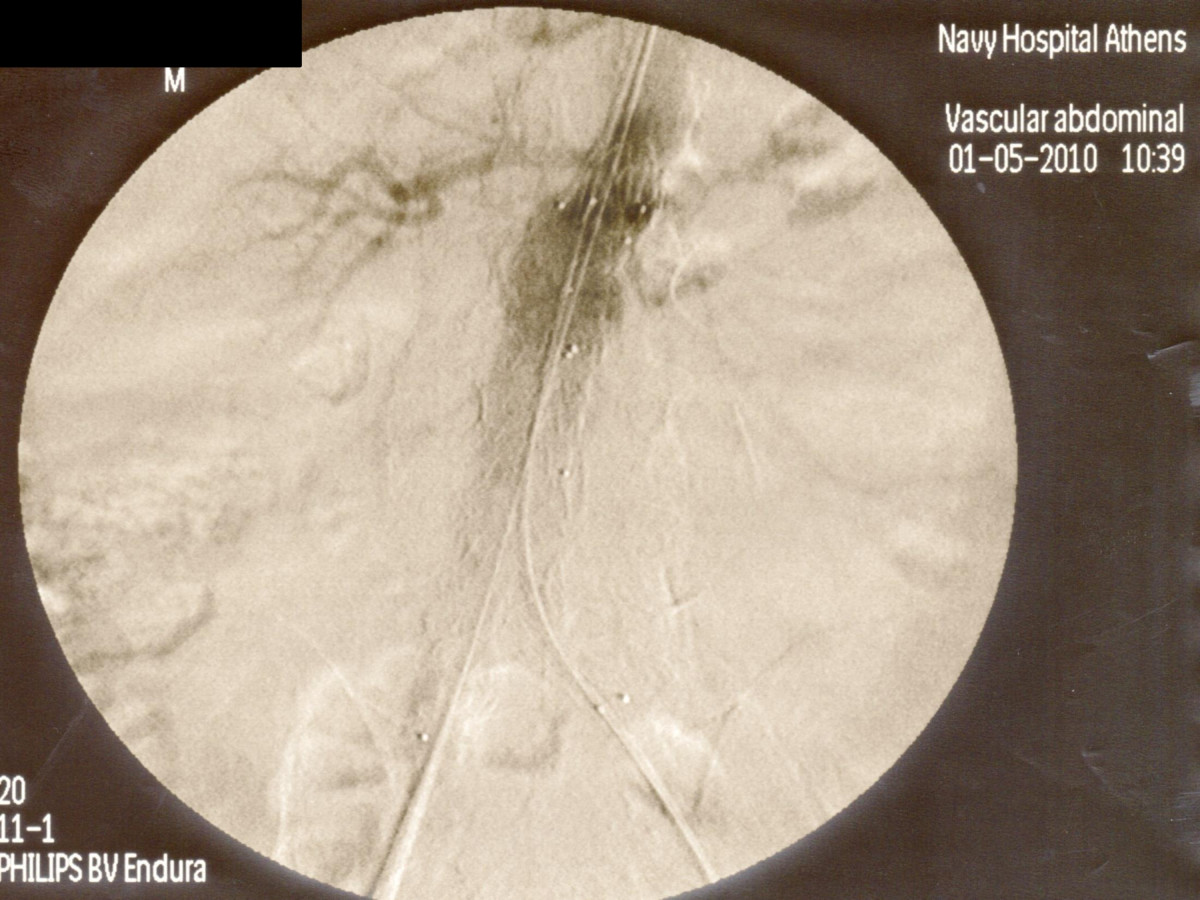

Ενδαγγειακή αποκατάσταση ανευρυσμάτων κοιλιακής αορτής

12ο Πανελλήνιο Συνέδριο Αγγειακής και Ενδαγγειακής Χειρουργικής

2010, Αθήνα